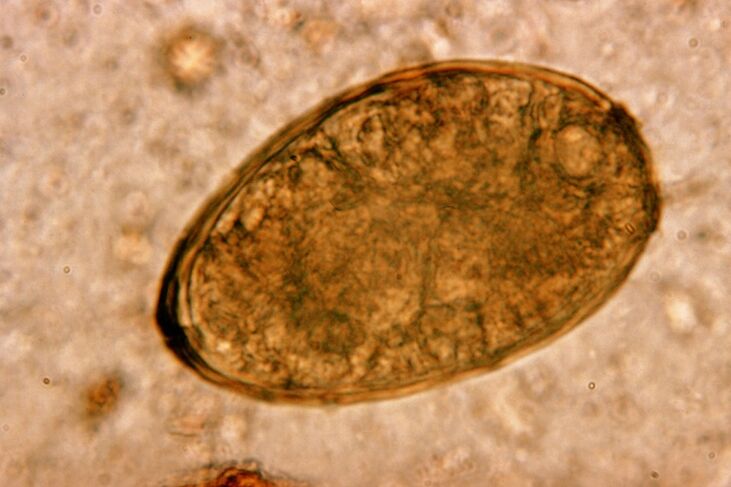

The small helminth lungworm, belonging to the class of trematodes, “specializes” in parasitizing specifically in the lungs.It causes much more serious problems in the respiratory system than roundworms, for example.

At the site of its location, infiltrates appear and hemorrhages develop, as a result of which cavities appear filled with decaying metabolites of worms, dead parasites and lung tissue.The damage caused by lungworm is further compounded by the fact that it is a long-liver and can live in the host's body for up to 20 years.